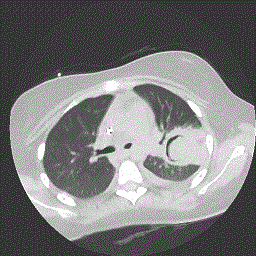

Besides Candida species, Aspergillus is by far the most common cause of IFD. The respiratory tract including lungs and sinuses, is the most common primary site of interest. In approximately 30% of cases, the infection spreads to other organs, such as the brain and the skin [2,4]. Exact data concerning the incidence of invasive aspergillosis (IA) are difficult to obtain. First, there are many factors related to the environment. For example, construction site in the neighborhood of the ward leads usually leads to an increase in infections [5]. Secondly, the use of prophylaxis and the incidence of resistance vary from center to center [6]. Another obstacle is that in children, clinicians might be reluctant to perform more invasive diagnostic tests such as bronchoalveolar lavage or a biopsy, leading to a lack of information concerning the exact pathogen involved (Figures 1 and 2). Still, data indicate that Aspergillus Fumigatus is the most frequent cause of IA and that other species such as A. Flavus are much more rare [2].

Imaging studies are fast and easy to access. Usually, CT scan remains the study of choice as standard radiography is usually not sensitive enough, especially in immunocompromised children lacking neutrophils. In adult patients, there are specific findings such as the halo sign, pulmonary nodules, and the air crescent sign and, in severe cases, cavitation [8]. However, these findings are much less obvious in children [4,8,9]. A single center review study conducted by Thomas et al showed that children had less specific findings such as segmental and multilobar consolidation, perihilar infiltrates, multiple small nodules, peripheral nodular masses and pleural effusions. Small cavitating nodules were present on CT in two of eight children [9,10]. Therefore, in high risk patients with radiological abnormalities treatment should be initiated as soon as possible, preferably after a tissue specimen has been obtained [2].

image   image

Figure 1   Figure 2